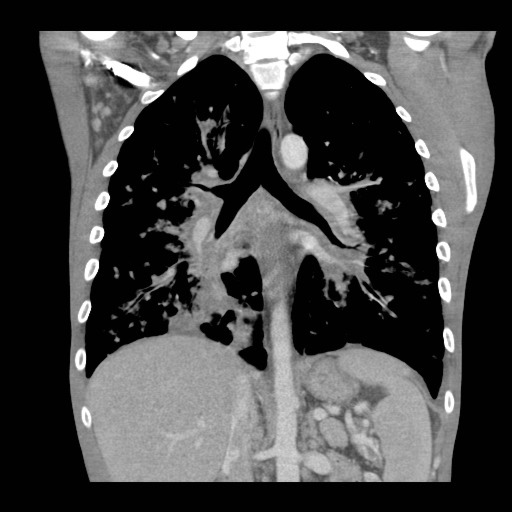

Gallery Lung Cancer Miscell KS cor 1b

KS cor 1b